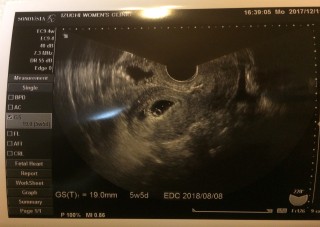

写真:5w5d:ゆーちゃんさん

昨日から少し出血があり急遽病院に行ってきました。

8ミリから19.8ミリまで成長していました。卵黄嚢も見えました。

来週には心拍確認できるかな?